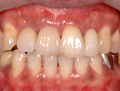

5:装置の装着 |

人工歯を装置して完了です。 |